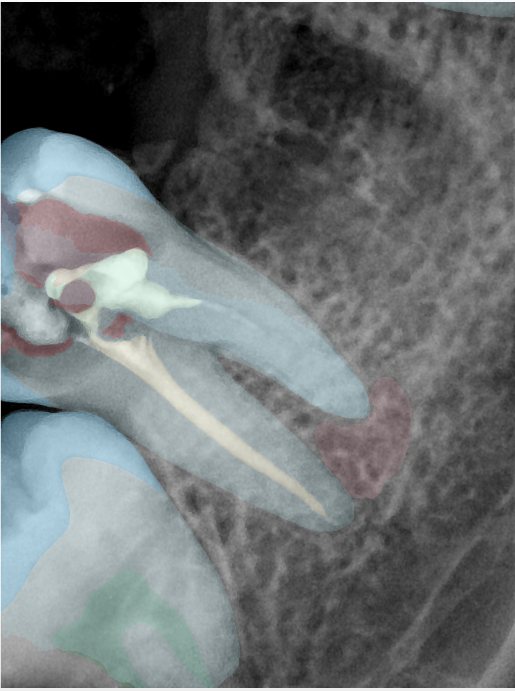

CR/DR 牙齿分割阶段记录

当前进展

- 完成了 CR/DR 牙齿相关分割训练

- 当前结果已经达到阶段预期,但仍有细节问题需要继续处理

相关测试

遇到的问题

- 训练过程中出现过 mask 下移问题

- 部分结果会出现 box 填充异常

- mask 边缘仍然有比较明显的锯齿感

参考

第二版算法问题测试